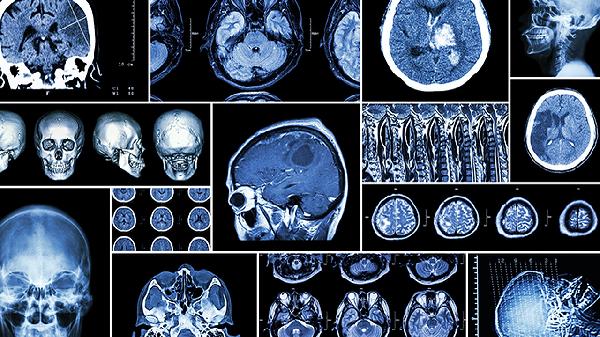

若摔傷后出現(xiàn)噴射狀嘔吐、瞳孔不等大或持續(xù)昏睡,可能提示硬膜下血腫或腦震蕩。嬰兒腦組織含水量高,外力作用下易發(fā)生彌漫性軸索損傷,需通過頭顱CT排除出血。早產(chǎn)兒或維生素K缺乏的患兒更易發(fā)生遲發(fā)性顱內(nèi)出血,即使當(dāng)時(shí)無癥狀也建議72小時(shí)內(nèi)密切監(jiān)測(cè)。避免搖晃寶寶頭部,哺乳時(shí)保持頭部略高于身體。